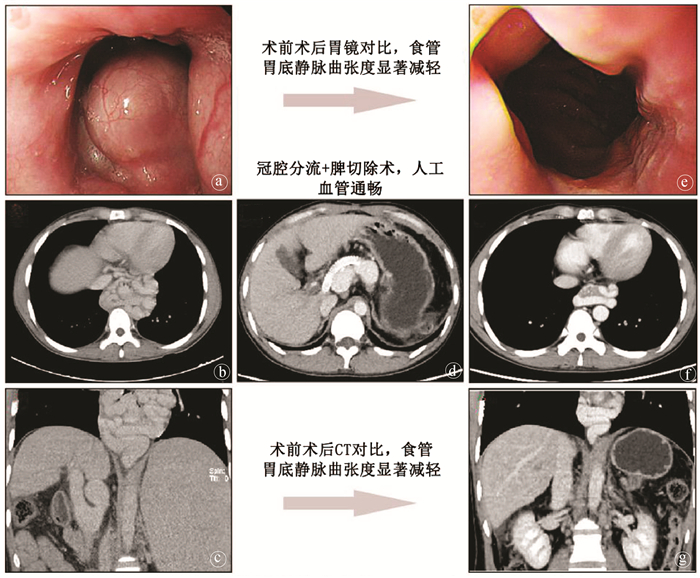

Value of coronary-caval shunt combined with splenectomy in portal hypertension

Weijie WANG, Rongtao ZHU, Ruopeng LIANG, Jian LI, Chixian ZHANG, Dexu LI

2021, 37(4): 898-901. DOI: 10.3969/j.issn.1001-5256.2021.04.034

Abstract(860) HTML (233) PDF (4530KB)(65)

Abstract: